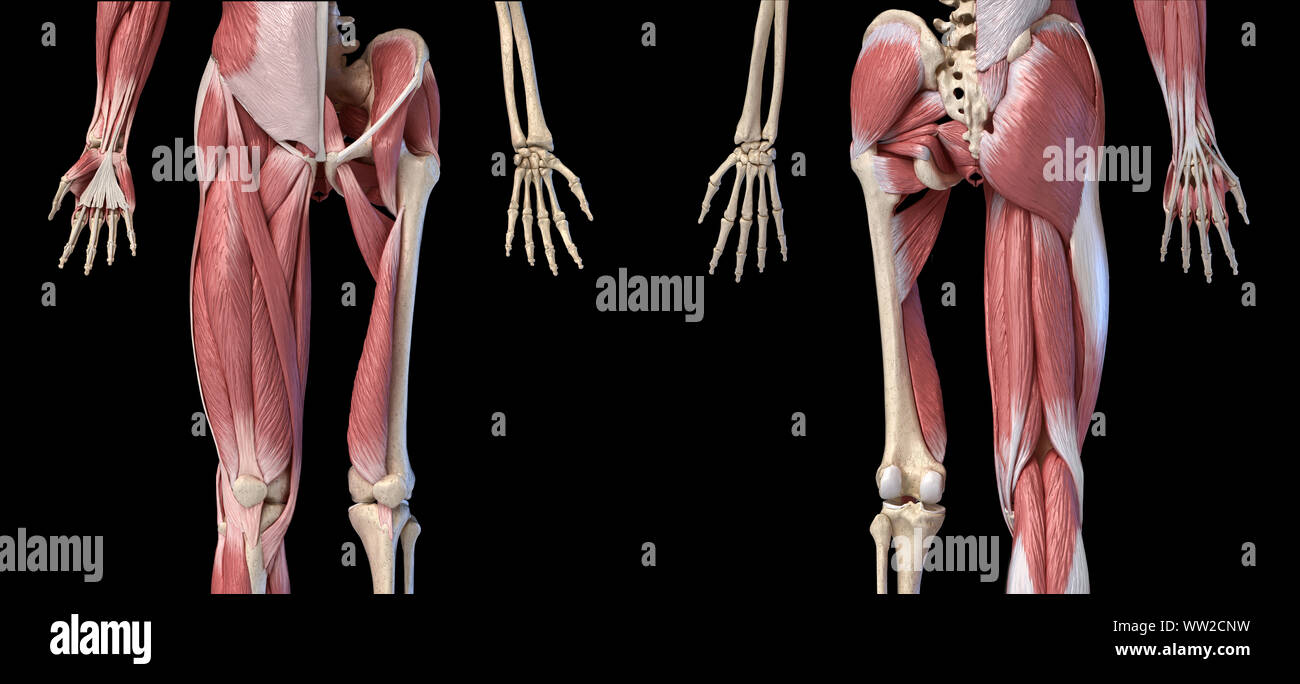

RFWW2CNW–Die männliche Anatomie, Gliedmaßen und hip Muskel- und Skeletterkrankungen Systeme, mit interner Muskelschichten. Vorder- und Rückansicht. schwarzen Hintergrund. 3d-Abbildung.